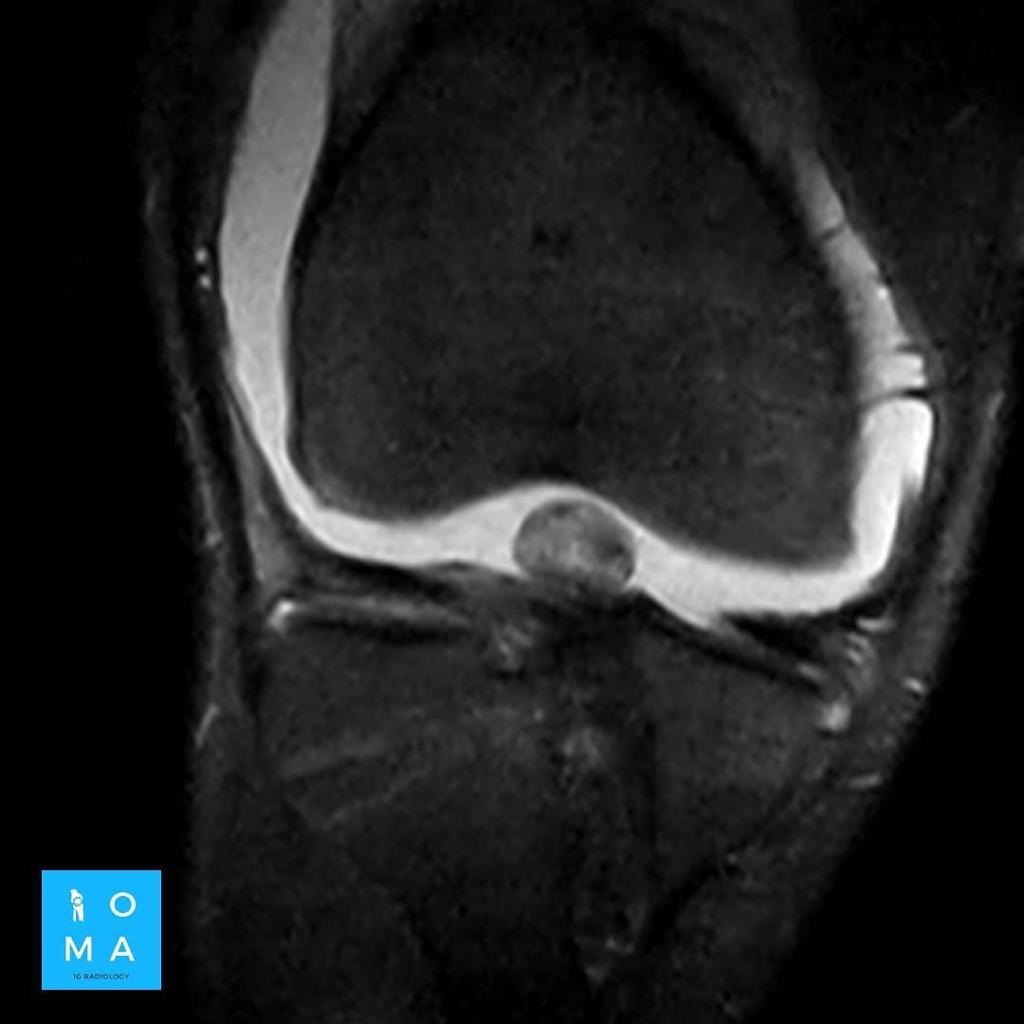

Se presenta caso de paciente de la 3a década, que en su embarazo se diagnostica con sospecha de adenoma y posterior al embarazo se realiza estudio de control contrastado para su mejor diferenciación.

En la evaluación con medio de contraste, se evalúa la relación arterial y de las venas, esto puede servir para buscar la arteria central relacionada con la hiperplasia nodular focal o bien, para evaluar la relación con las estructuras vasculares que son muy importantes para el planeamiento quirúrgico .

en este caso, aún cuando los hallazgos son atípicos tanto para hiperplasia nodular focal como para adenoma, nos inclinamos hacia el diagnóstico de adenoma debido a los antecedentes de la paciente, el tamaño de la lesión, el área de sangrado, el contenido de grasa.